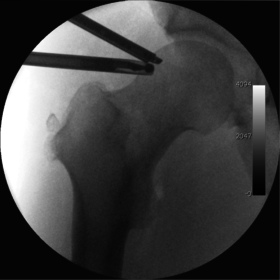

![]() Intraoperative fluoroscopic image during an arthroscopic resection of a cam lesion of the femur. The upper instrument is the arthroscope (viewing device), while the lower is the high-speed burr used for reshaping the bone. |

Technique

The procedure is performed with the patient asleep (general anaesthetic) or under spinal anaesthesia. There are two widely used methods, one with the patient on their back (supine) and the other on their side (lateral decubitus). Which is used is down to the surgeon's preference. To gain access to the central compartment of the hip joint (between the ball and socket), traction is applied to the affected leg after placing the foot into a special boot. (See fig. 2) There is specifically designed equipment for this, although some surgeons use a 'traction table', initially designed to help in the operative fixation of broken thigh and lower leg bones. The amount of traction (or pull) needed is assessed with the help of fluoroscopy (low-dose portable x-ray). (See fig. 3) It is usually not possible to distract the ball from the socket with traction alone by more than a few millimetres. Once the surgeon is happy that he will be able to gain access to the hip joint (i.e. the ball will distract from the socket by a small amount), the patient is then painted with antiseptic and the surgical drapes applied.

Standard arthroscopic treatment of symptomatic cam FAI involves debridement (resection) or repair of any labral [10] and chondral injuries [11] in the central compartment of the hip, and subsequent reshaping of the head-neck junction of the upper femur (osteochondroplasty) in the peripheral compartment [12][13] using high-speed motorised burrs that are similar in design to a dentist's drill (see fig. 9).